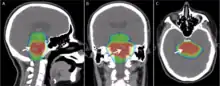

Virtual simulation, and 3-dimensional conformal radiation therapy

The planning of radiation therapy treatment has been revolutionized by the ability to delineate tumors and adjacent normal structures in three dimensions using specialized CT and/or MRI scanners and planning software.[76]

Virtual simulation, the most basic form of planning, allows more accurate placement of radiation beams than is possible using conventional X-rays, where soft-tissue structures are often difficult to assess and normal tissues difficult to protect.

An enhancement of virtual simulation is 3-dimensional conformal radiation therapy (3DCRT), in which the profile of each radiation beam is shaped to fit the profile of the target from a beam's eye view (BEV) using a multileaf collimator (MLC) and a variable number of beams. When the treatment volume conforms to the shape of the tumor, the relative toxicity of radiation to the surrounding normal tissues is reduced, allowing a higher dose of radiation to be delivered to the tumor than conventional techniques would allow.[10]

With Godfrey Hounsfield's invention of computed tomography (CT) in 1971, three-dimensional planning became a possibility and created a shift from 2-D to 3-D radiation delivery. CT-based planning allows physicians to more accurately determine the dose distribution using axial tomographic images of the patient's anatomy. The advent of new imaging technologies, including magnetic resonance imaging (MRI) in the 1970s and positron emission tomography (PET) in the 1980s, has moved radiation therapy from 3-D conformal to intensity-modulated radiation therapy (IMRT) and to image-guided radiation therapy tomotherapy. These advances allowed radiation oncologists to better see and target tumors, which have resulted in better treatment outcomes, more organ preservation and fewer side effects.[121]